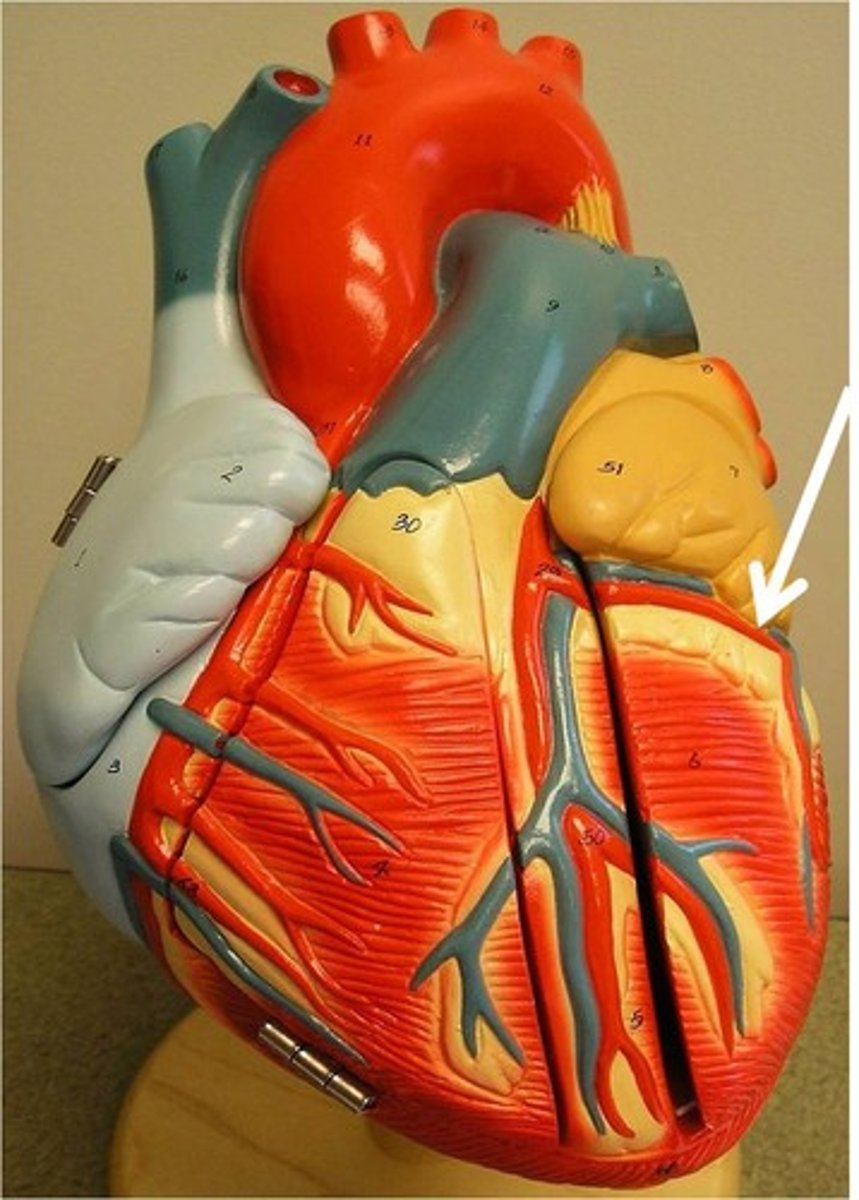

right coronary artery

left coronary artery

descending aorta